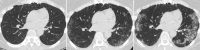

As lung transplantation has become the most effective definitive treatment option for end-stage chronic respiratory diseases, yearly rates of this surgery have been steadily increasing. Despite improvement in surgical techniques and medical management of transplant recipients, complications from lung transplantation are a major cause of morbidity and mortality. Some of these complications can be classified on the basis of the time they typically occur after lung transplantation, while others may occur at any time. Imaging studies, in conjunction with clinical and laboratory evaluation, are key components in diagnosing and monitoring these conditions. Therefore, radiologists play a critical role in recognizing and communicating findings suggestive of lung transplantation complications. A description of imaging features of the most common lung transplantation complications, including surgical, medical, immunologic, and infectious complications, as well as an update on their management, will be reviewed here. Keywords: Pulmonary, Thorax, Surgery, Transplantation Supplemental material is available for this article. © RSNA, 2021.